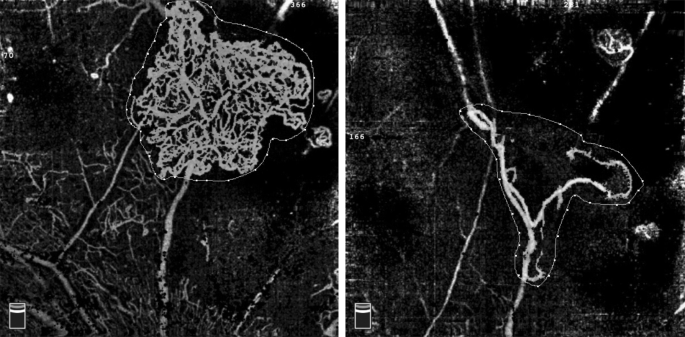

The use of anti-VEGF drugs has demonstrated a positive effect in regressing NV. It has also been shown that repeated injections of such drugs could improve vision in PDR patients. The main shortcomings of anti-VEGF agents are the short duration and relatively high cost for some patients, but such drugs may also act as adjuvant agents to PRP in improving the response to treatment. A recent multi-centre study by Figueira et al. [7] compared the efficacy of ranibizumab plus PRP vs. PRP alone over a 12-month period and reported a total regression of NV in 43.9% of eyes in the combination group vs. 25.0% in the PRP group, showing the superiority of combination treatment, similarly to other FFA studies [5, 6]. In addition, eyes administered combination treatment might receive fewer laser burns and may be associated with fewer side effects such as pain, macular oedema, and central vision loss. Our study using OCTA to describe NVE changes revealed that the significant reduction in NVE started as early as 1 week after the injection and lasted until 6 months after treatment (Fig.Ā 3). Compared with the PRP group, the NVE reduction observed in the combination group was significantly larger at all study visits, suggesting that combination treatment could cause a quick and durable regression of retinal neovascular tissues. Although only one single dose of anti-VEGF was applied in this combination approach, it showed a synergistic effect with PRP causing an eventual reduction in NVE, as in previous studies using multiple injections [7], suggesting the combination approach to be a cost-effective choice for PDR patients. As for BCVA changes, there was no statistically significant difference between the two groups at any visits, whereas significant visual acuity improvement was only observed in the PRP group at 3 months. Similar findings were reported by Figueira et al. [5, 7]. Possible explanations include the limited number of patients who had fairly good baseline visual acuity but were unassociated with DME. In the Diabetic Retinopathy Clinical Research network study [19], 35% of cases in the PRP group were given ranibizumab at baseline due to DME, and this treatment might be related to the significantly improved BCVA reported in this study.

To the best of our knowledge, this is also the first study to use OCTA to observe longitudinal changes in NVE treated by different methods. Previous studies have described preretinal NV in PDR using OCTA [21] and have reported the temporal profile of the response of neovascularization of the disc size to a single intravitreal bevacizumab injection within a 30-day period [9]. The changes in NVE over time could be established with frequent and repeated OCTA examination, which is impossible when using FFA due to its invasive nature. The current limitations of OCTA imaging lie in the following aspects. First, accurate NVE assessment could hardly be achieved when the NVE size is beyond the detectable range of the instrument. Second, the absence of signals on OCTA indicates the absence of flow but does not exclude patent vessels with very slow blood flow below the detection threshold, thus leading to the underestimation of NVE. Third, in some cases, there might be disagreements between OCTA and FFA in the diagnosis of NVE. In one of our cases, shrinking NVE was present on OCTA images 1 year after PRP, but no evident fluorescein leakage was observed on FFA (Fig.Ā 4), suggesting that the function of endothelial cells in these residual blood vessels may have improved. Since not all included cases were followed by FFA beyond 6 months after treatment, whether this phenomenon generally exists or not as well as how these blood vessels may develop remains unclear.